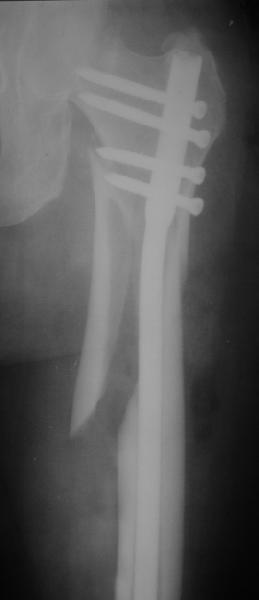

В частности, его возможности при фиксации переломов проксимального отдела бедра - в сравнении с другими, имеюшими лишь по одному статическому и динамическому отверстию и с кондуктором для введения 2 винтов.

Это было года 2,5 назад, мы тогда еще уточняли возможности шинирования с угловой стабильностью гвоздем с поперечным расположением винтов при переломах проксимального отдела бедра. Пациенту не пришлось приобретать намного более дорогой рекон или проксимальный гвоздь. В приложении еще несколько примеров применения того гвоздя при высоких переломах бедра, в том числе с более латеральной точкой входа. Гвоздь изгибаем для этого.